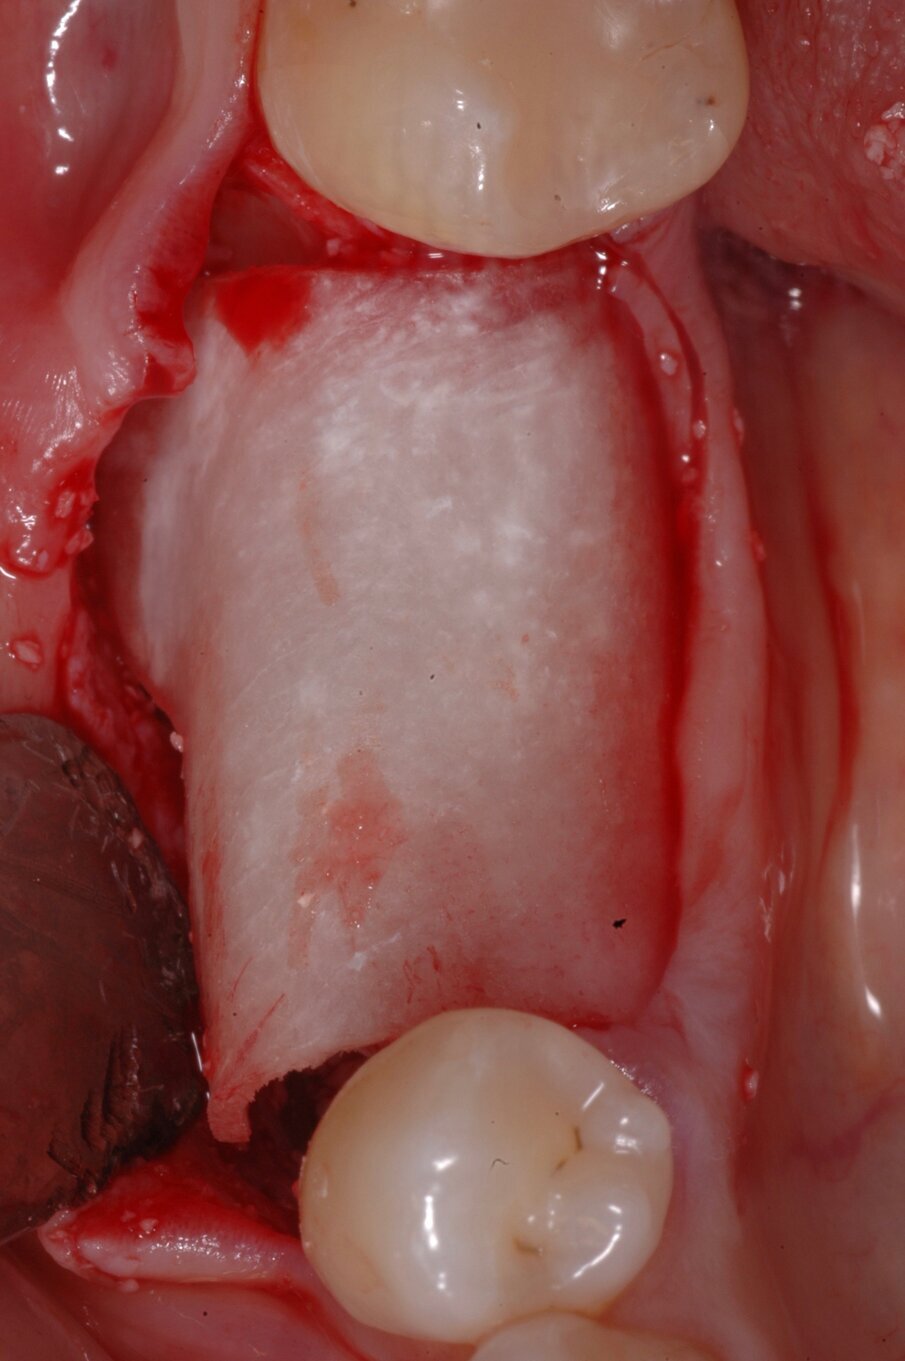

La lamina corticale è una membrana semirigida di osso corticale suino collagenato (Lamina OsteoBiol, Tecnoss, Giaveno, Italy) che offre nello stesso tempo rigidità e parziale flessibilità, stabilizzandosi con l’anatomia locale e favorendo la neoformazione ossa nello spazio che si viene a creare al di sotto di essa12 (Figg. 5, 6). In questo caso dopo aver somministrato alla paziente anestesia locale con Articaina 1:200.000 i due lembi vestibolare e linguale venivano sollevati con scollamento a tutto spessore dopo aver effettuato con lama 15c un incisione a mezza cresta. L’anatomia evidenziava quanto già visto nelle sezioni della CBCT, cioè una cresta assottigliata e appuntita con grave deiescenza vestibolare. La lamina corticale curva di spessore di 1 mm e lunghezza di 35 mm venne estratta dalla sua confezione sterile e modellata per adattarsi e stabilizzarsi alla zona interessata. La stessa venne tagliata e modellata in maniera tale da ingrandire in spessore e altezza la zona interessata ma nel rispetto dell’anatomia locale, perciò creando un incisione a “V” nella zona vestibolare che, da una parte consentisse al nervo alveolare inferiore di emergere, dall’altra di appoggiare la lamina al gradino creato dal nervo nella sua emergenza per migliorare la stabilità della lamina stessa.

Sulla cresta ossea deiescente vennero eseguite perforazioni con una fresa a lancia per stimolare sanguinamento e compartecipazione delle cellule del midollo osseo nella colonizzazione dell’innesto osseo (Figg. 7, 8). Come materiale da innesto in questo caso venne utilizzato osso autologo raccolto nella parte palatale con un grattino, associato a particolato eterologo collagenato Gen-Os (OsteoBiol, Tecnoss, Giaveno, Italy) idratato con il coagulo del paziente14. Questo agglomerato genera una base sulla quale la lamina corticale rappresenta il “coperchio” di protezione che favorisce la rigenerazione ossea, una volta inserita la lamina in posizione, l’aspetto della nuova cresta ossea si presenta incrementato fino a 8-9 mm. (Fig. 9). L’intervento viene completato con la perfetta chiusura dei lembi dopo che gli stessi sono stati rilasciati grazie a un’incisione orizzontale a livello del muscolo che ne consente l’allungamento.